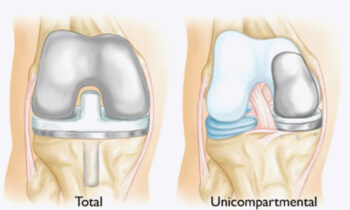

Unicompartmental Knee Surgery In Nagpur Unicompartmental knee surgery In Nagpur By Dr. Abhishek Bhalotia, practicing at Asian Institute Of Advanced Surgeries, It is an advanced orthopaedic procedure designed to...

Selective Knee Replacement Procedure (United SSH) in Nagpur Selective Knee Replacement Procedure (United SSH) in Nagpur By Dr. Abhishek Bhalotia, practicing at Asian Institute Of Advanced Surgeries,It is an...

Targeted knee joint treatments In Nagpur Targeted knee joint treatments In Nagpur By Dr. Abhishek Bhalotia, practicing at Asian Institute Of Advanced Surgeries, focus on identifying the exact source...